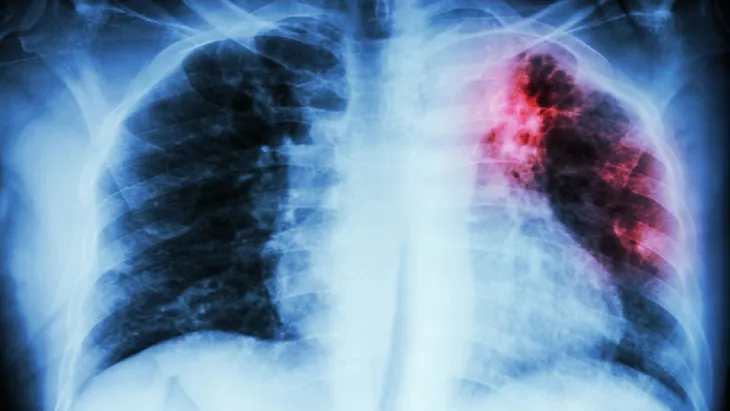

La vacuna BCG fue desarrollada para prevenir las formas graves de tuberculosis (TB), una enfermedad infecciosa que, aunque es prevenible y curable, sigue siendo un problema vigente en el país.

La tuberculosis es causada por el bacilo de Koch y se transmite de persona a persona a través del aire, al toser, estornudar o incluso hablar. El contagio es más frecuente en contextos de convivencia prolongada como el hogar, la escuela, el trabajo o espacios institucionales.

En este escenario, el fin de la vacuna BCG es proteger a niñas y niños de las formas más graves de la enfermedad como la meningitis tuberculosa o osteomielitis.

La vacunación, junto con el diagnóstico oportuno y el tratamiento adecuado, constituye la tríada fundamental para el control de la tuberculosis.

Según datos del Boletín Epidemiológico del Ministerio de Salud, en el AMBA se registraron 19.915 casos de TB entre 2023 y 2024, con un incremento sostenido en el segundo período. Estas cifras refuerzan la necesidad de sostener y fortalecer las estrategias de prevención.